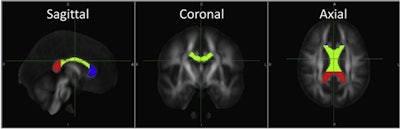

DTI-MR images are examples of the corpus callosum and its substructures -- genu (blue), body (green), and splenium (red) -- used in this study, as defined by software from Johns Hopkins University. Image courtesy of the European Journal of Radiology.Through DTI, the researchers targeted mean fractional anisotropy values in the corpus callosum and its substructures -- genu, body, and splenium -- which are believed to serve an important role in cognition and neural communication. Structural MR images were used to score the severity of brain injuries based on the number of lobes affected, volume and type of white-matter injury, and grey-matter damage.